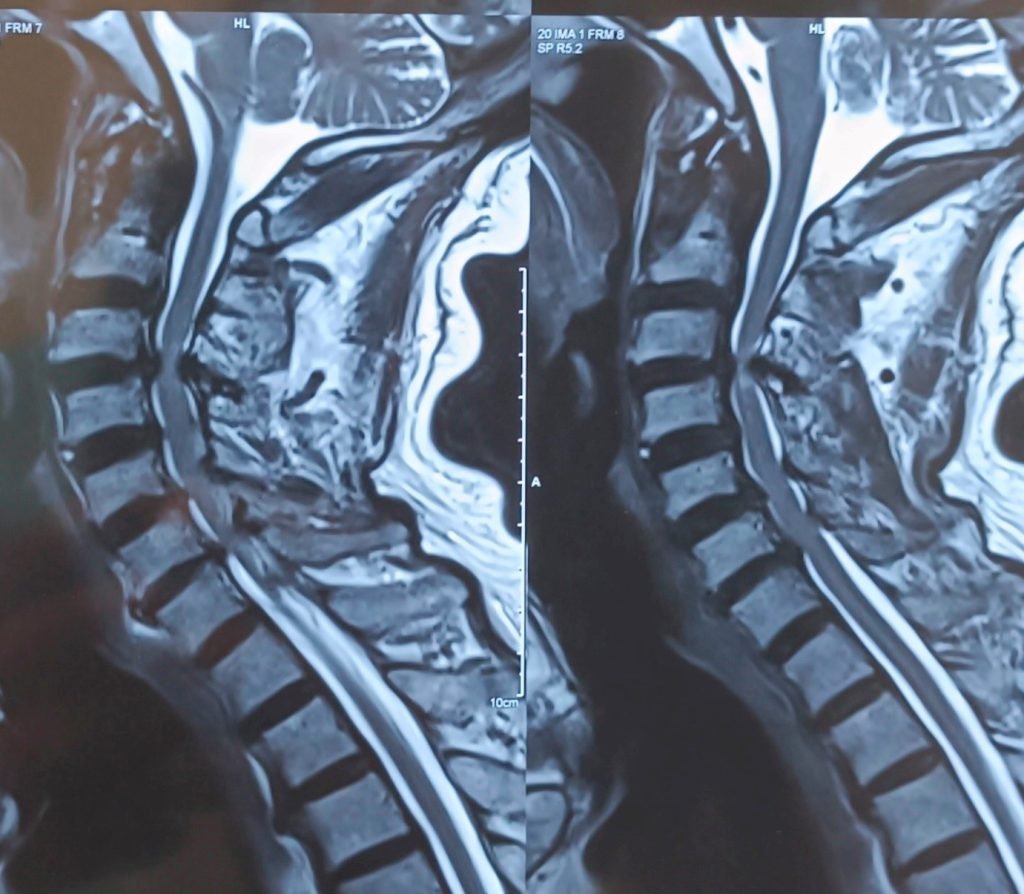

Cervical Myelopathy is a serious spinal condition in which the spinal cord in the neck (cervical spine) becomes compressed. This compression is most commonly caused by degenerative changes in the spine, such as cervical disc prolapse, spinal canal stenosis, bone spur formation, or thickening of spinal ligaments. When the spinal cord is compressed, normal nerve signal transmission is affected, leading to problems with movement, coordination, and sensation.

Diagnosis

Accurate diagnosis is essential for effective treatment. Dr. Nitish Agrawal uses:

- MRI of the cervical spine (gold standard investigation)

- X-rays and CT scans to assess spinal alignment and bony compression